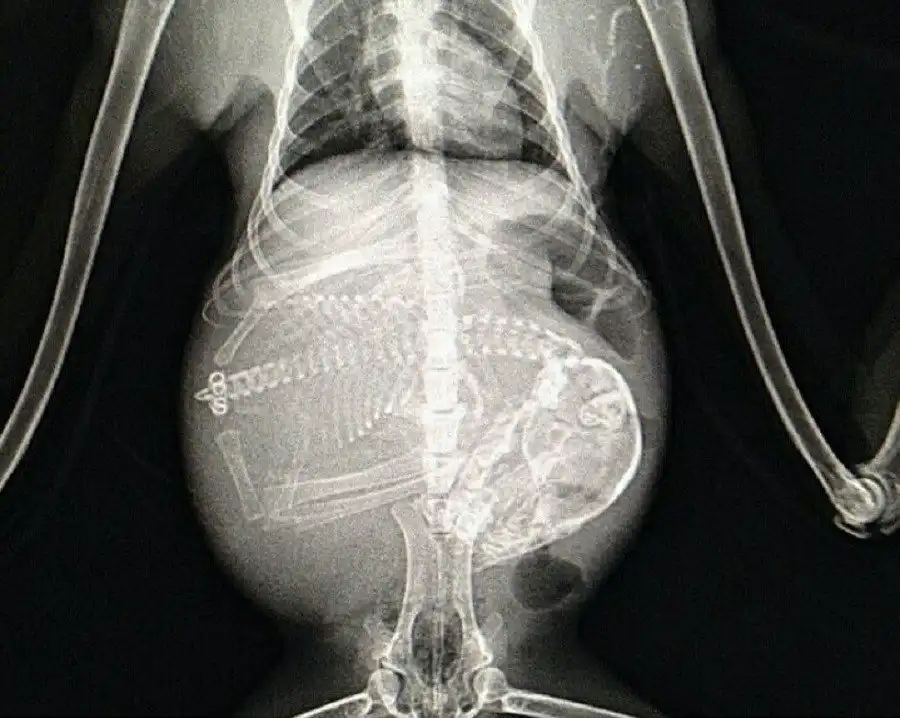

Беременная летучая мышь